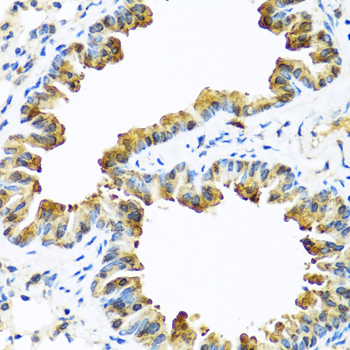

Immunohistochemistry of paraffin-embedded mouse lung using SERPINA10 antibody.